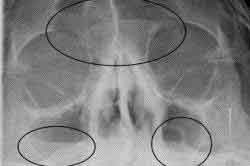

При проведении рентгенографии гайморита можно заметить чёткий контраст между чёрными пазухами и белым инфильтратом, что часто называют симптомом «молока в стакане». Если рентгенолог видит этот симптом в двух проекциях, то диагноз гайморита подтверждается. При гнойном гайморите также наблюдается чёткое затемнение области гайморовых пазух при проведении исследования в боковой и прямой проекциях.

Если в полости носа есть жидкость, то на рентгенограмме будет видно затемнение. Врач может привести примеры рентгенограмм, чтобы проиллюстрировать этот факт. Он объясняет, что выявление гайморовых пазух не зависит от уровня или типа затемнения на снимке. Наличие затемнения не всегда означает наличие гайморита. Точно так же нельзя сразу определить наличие фронтита. Гайморит представляет собой воспалительное заболевание пазух носа, в которых может накапливаться различного вида жидкость.

При этом заболевании на рентгеновском снимке можно увидеть черные области в пазухах, содержащие светлое инфильтративное вещество. Врач может определить наличие патологии по резкому контрасту на снимке и отличить её от нормального состояния. Важно помнить, что подобное изображение на рентгене не всегда указывает на наличие заболевания. Поэтому не следует заниматься самолечением, а сразу же обратиться к отоларингологу для консультации. После установления диагноза гайморита врач назначит соответствующее лечение.

- Появление затемнений над носом указывает на развитие воспаления в лобных пазухах.

- Затемнения в нескольких областях могут свидетельствовать о воспалительном процессе в различных местах.

Накопление гнойного материала в синусах при гайморите можно увидеть на изображении как светлое пятно на фоне темной полости. При значительном объеме содержимого можно разглядеть его горизонтальную линию.

Иллюстрация здоровых пазух напоминает темные полуовальные полости, расположенные по обе стороны от носа. Они имеют одинаковую окраску и соответствуют глазницам. Это свидетельствует об отсутствии любых патологий. Появление даже маленьких светлых областей будет указывать на начало воспалительных процессов. Чем сильнее воспаление, тем ярче белые пятна. Кроме того, изображение носовых пазух изменится. При гайморите на рентгеновском снимке пазухи носа будут иметь неровные контуры и утолщенные стенки.

Начало патологического процесса связано с воспалением синусов лица. Позднее воспалительный процесс распространяется на лобные области. Рентгенологически это проявляется в виде затемненных областей над носом. Часто воспалительные процессы развиваются одновременно в лобных и боковых синусах. Эти признаки указывают на наличие нескольких заболеваний, таких как гайморит и фронтит.